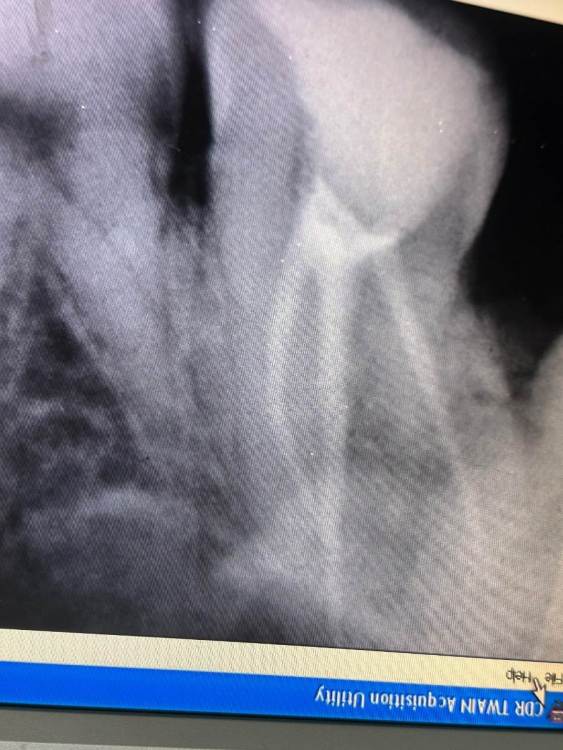

Здравствуйте!16 дней назад пролечили 7 верхний зуб. Сразу после началась сильная боль, которая держалась 2 дня и потом пошла на спад. На 7 день она остановилась и держится на одном месте. Зуб реагирует когда постучишь по временной пломбе. Когда поешь, потом начинал ныть. Так же легкие, редкие распирающие и пульсирующие боли. На зуб Накусывать неприятно. Несколько раз ломило от него все зубы, а до него было больно даже языком дотронуться.  В легком дискомфорте все это сохранялось 7 дней. На 13 день доктор распломбировала каналы, зуб поболел после распломбировки день, после вмешательства, как все утихло  и опять  я чувствую тот же дискомфорт, т е после распломбировки каналов ничего не изменилось, все держится на одном месте. сейчас в каналах кальций.Возможно ли что каналы зря распломьировали?  И проблема не в них. При удалении нерва доктор сказал, что кровь из канала не останавливалась, но потом промыла вроде остановилась и она его запломбировала.

Здравствуйте, скорее всего дело в четвертом канале, который пропустили(не нашли) и не обработали.  Сделайте КТ,  там видно будет,  что с четвертым каналом.